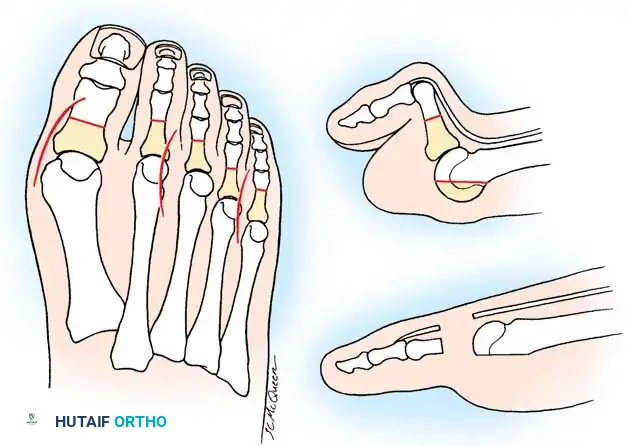

Surgical Diagrams demonstrating the principles of first MTP arthrodesis and lesser metatarsal head resection to restore a functional, plantigrade forefoot cascade.

Arthrodesis of the first ray provides a stable medial column, which is essential for offloading the lesser metatarsals and preventing recurrent lateral deformity.

1. Approach: A dorsal longitudinal incision is made medial to the EHL tendon, extending from the mid-shaft of the first metatarsal to the interphalangeal joint.

2. Joint Preparation: The capsule is incised, and the collateral ligaments are released. The severely eroded articular surfaces of the first metatarsal head and the base of the proximal phalanx are resected. Cup-and-cone reamers are highly recommended to preserve length while allowing multi-planar adjustment.

3. Positioning: The hallux is positioned in 10 to 15 degrees of valgus and 15 to 20 degrees of dorsiflexion relative to the first metatarsal shaft. Neutral rotation must be confirmed to ensure the toenail faces directly dorsal.

4. Fixation: Rigid internal fixation is achieved using a dorsal contoured titanium plate and a lag screw across the arthrodesis site.

Step 3: Lesser Metatarsal Head Resection

- Approach: Two dorsal longitudinal incisions are typically utilized (one centered between the 2nd and 3rd rays, and one between the 4th and 5th rays) to access all lesser MTP joints while preserving dorsal skin bridges. Alternatively, a transverse plantar approach can be used if severe plantar callosities require excision.

- Resection: The extensor tendons are retracted or lengthened (Z-plasty). The dorsal capsule is opened, and the collateral ligaments are sharply divided to allow plantarflexion of the metatarsal.

- Osteotomy: An oscillating saw is used to resect the metatarsal heads at the anatomical neck. It is imperative to create a smooth, parabolic cascade (the 2nd metatarsal should be the longest, tapering down to the 5th).

- Soft Tissue Balancing: The plantar plate and fat pad, which have migrated distally, are mobilized and pulled proximally under the remaining metatarsal stumps. If the toes remain contracted, closed osteoclasis or PIP joint resection arthroplasties may be performed.

- Pinning: Smooth Kirschner wires (K-wires) are driven antegrade through the toes and retrograde into the metatarsal shafts to hold the toes in neutral alignment.